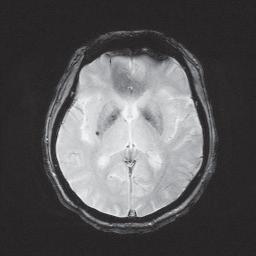

脑微出血在磁共振磁敏感加权序列上表现为小的、圆形,直径在5~10mm的信号缺失(图1)。影像学表现有扩大效应,也就是说MRI 上磁敏感序列上信号丢失的直径大于实际的病灶大小。MRI 扫描的参数不同,检测的敏感性有较大差异,使用长的回波时间、更短的层间间距、3D 影像检查、更高的场强和新的序列或磁敏感加权序列,可以使微出血检出率增加2~3 倍。要注意的是,脑微出血有可能因为血液流空、海绵状血管畸形、小梗死的出血转化、铁沉积、散在的钙化等被误诊为脑微出血。

图1 微出血在梯度自旋回波(GRE)上信号缺失

图片来源:首都医科大学附属北京天坛医院